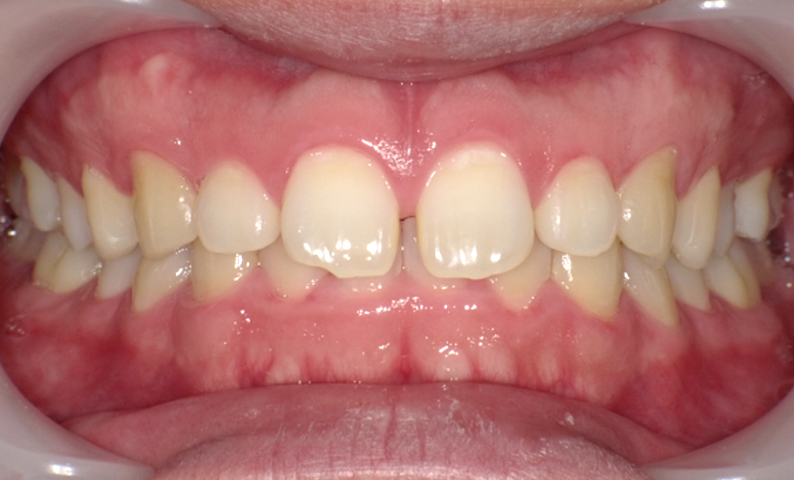

症例_001 前歯「すきっ歯」症例

治療期間:9ヶ月金額:51万円+税20代女性すきっ歯

| Before | After |

|---|---|

|